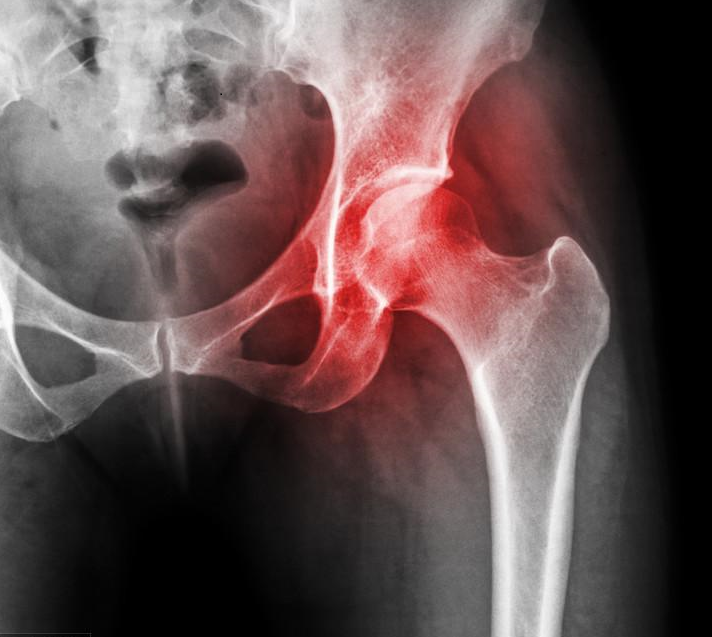

3.股骨头坏死:太多朋友问股骨头坏死能不能吃了。遗憾的告诉大家,作用及效果不大,尤其是X光片已经发现囊性变的患者。股骨头坏死有很多的分型,比如创伤型(就是骨折后形成的),这种源于骨折引起血运不佳,从而坏死。所以营养软骨是没用的,而是需要尽早改善血运和代谢。

股骨头坏死